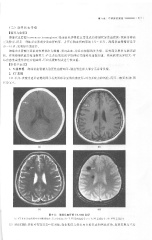

Page 323 - 医学影像诊断学